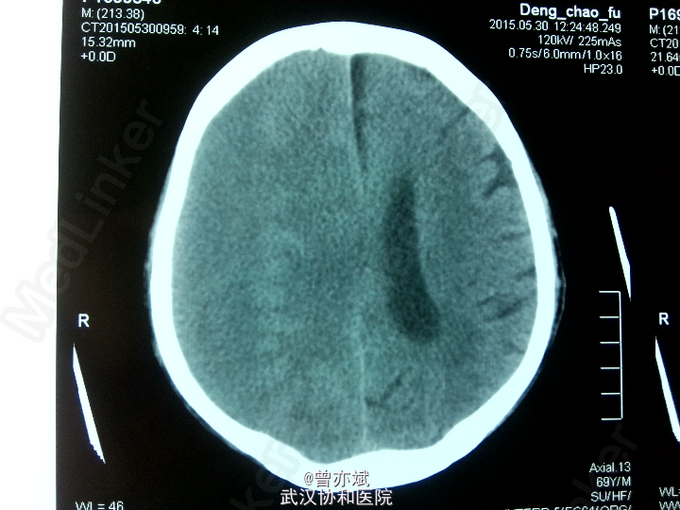

主诉:双下肢乏力3月余,加重1周 现病史:患者2月前意外摔倒后感双下肢乏力,无昏迷、恶心呕吐、头痛头晕等症状,未予特殊处理,今日感双下肢乏力加重,来我院就诊,行CT示右侧慢性硬膜下血肿。

诊断:慢性硬膜下血肿 处理:行微创钻孔引流术